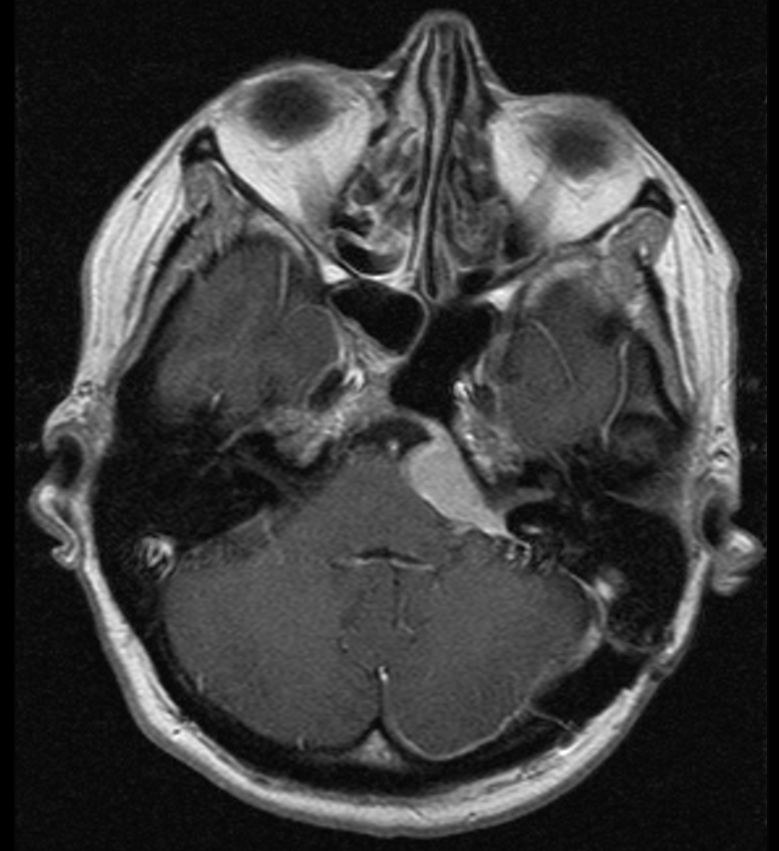

| Kleinhirn-Brückenwinkel |

47-jährige Frau, die vor 6 Jahren ein Kleinhirnbrückenwinkel-Meningeom entwickelte. Nach Operation Gehörverlust links und Stimmbandlähmung links. 2. Operation vor 3 Monaten. | ||||||

Danach fehlende Tränensekretion links und Parästhesien im Gesichtsbereich.![]() |